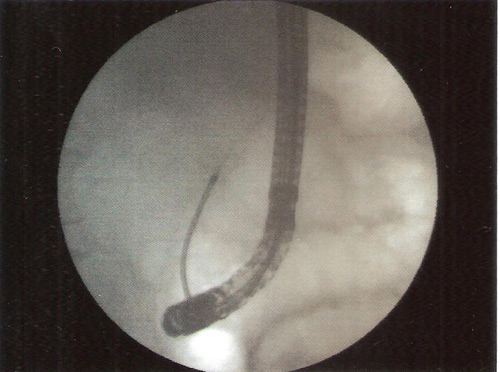

ERCP was performed.Selectuve cannulation was done of the pancreatic duct .The wire could negotiate the stricture in the neck but even a 5 Fr biliary dilator could not.A stent retriever was screwed over the wire and the stricture dilatation obtained with removal of fragments of stone.A pancreatic stent was placed .